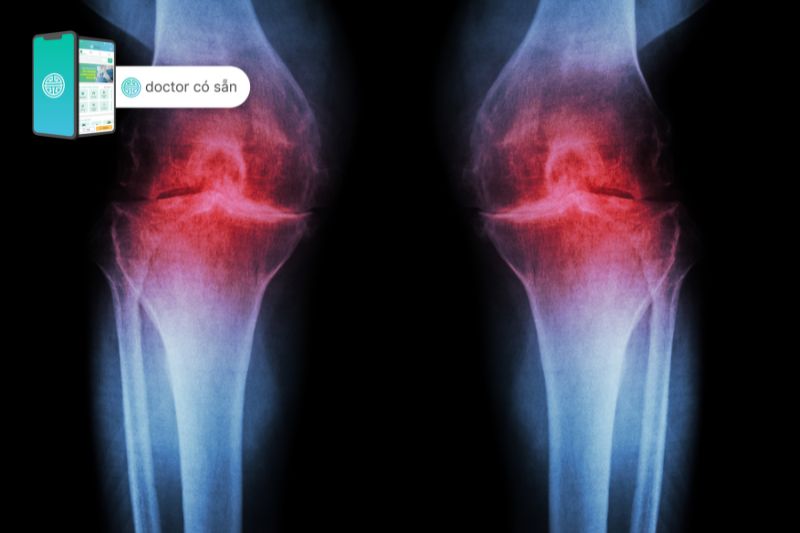

- Chụp X-quang: Chúng có thể tiết lộ tổn thương khớp gối ở giai đoạn sau nhưng có thể không phát hiện được những thay đổi ở giai đoạn đầu.